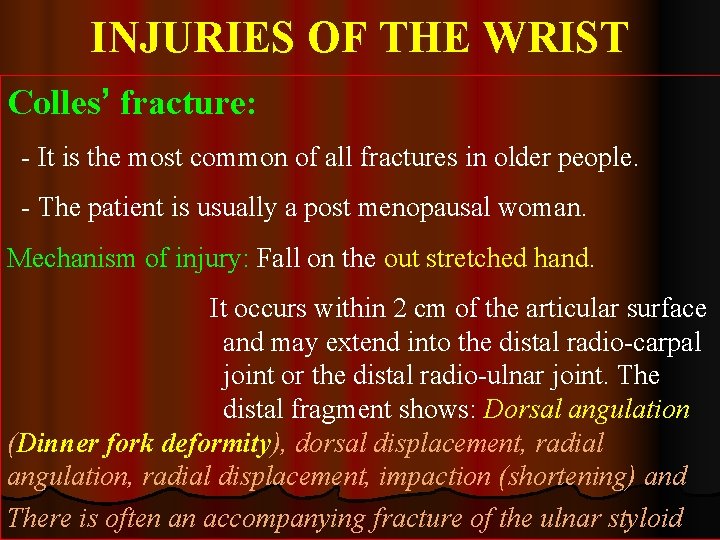

INJURIES OF THE WRIST Colles’ fracture: - It is the most common of all fractures in older people. - The patient is usually a post menopausal woman. Mechanism of injury: Fall on the out stretched hand. It occurs within 2 cm of the articular surface and may extend into the distal radio-carpal joint or the distal radio-ulnar joint. The distal fragment shows: Dorsal angulation (Dinner fork deformity), dorsal displacement, radial angulation, radial displacement, impaction (shortening) and There is often an accompanying fracture of the ulnar styloid